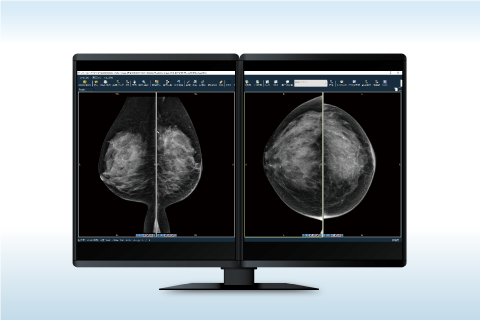

電子カルテ一体型ビューワ マンモグラフィービューワ

マンモグラフィービューワ